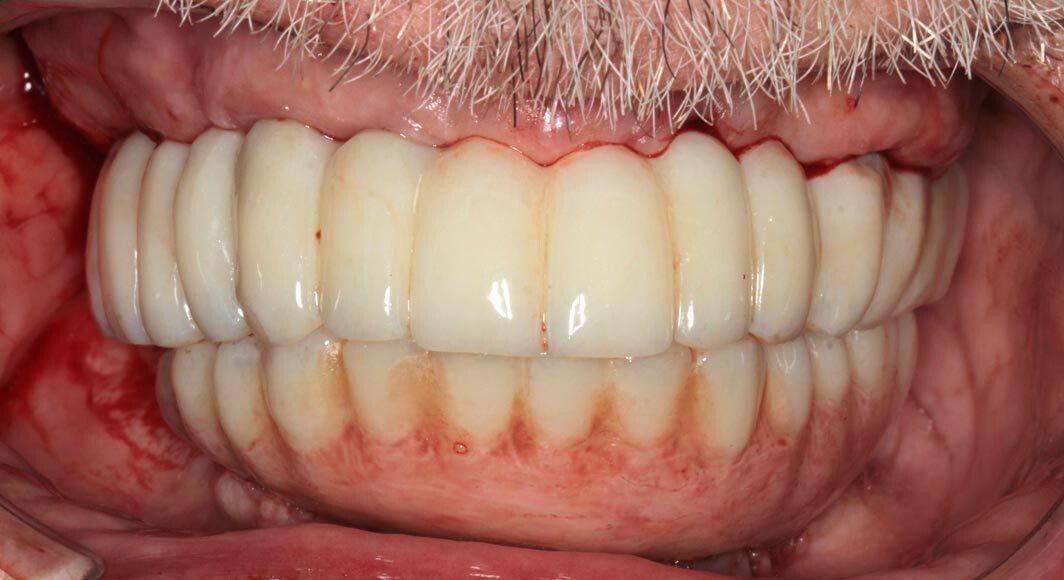

Prototype try-in, smile. The temporary bridges are removed and the prototypes placed. This is where the most scrutiny takes place as we want the patient and family to be thrilled with the appearance and bite. This is the last time changes can be made.